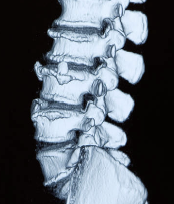

2. 디스크 문제와 신경 압박

허리 디스크가 돌출되거나 손상될 경우 주변 신경을 압박하여 저림이나 통증을 유발할 수 있습니다. 허리 디스크는 척추뼈 사이에 있는 물렁한 조직으로, 충격을 흡수하는 역할을 합니다. 하지만 장기간 잘못된 자세나 무리한 운동으로 인해 디스크가 돌출되면 허리뿐만 아니라 다리까지 저리는 증상이 나타날 수 있습니다. 특히 40대 이상에서 퇴행성 변화로 인해 디스크 문제가 발생하기 쉬운데요, 주기적인 체크와 치료가 필요합니다.

3. 척추 협착증

척추 협착증은 척추관이 좁아져 신경을 압박하는 질환으로, 주로 허리와 다리에 저림 증상을 유발합니다. 협착증은 주로 노화로 인해 발생하지만, 허리에 무리가 가는 활동이 반복될 때도 증상이 나타날 수 있습니다. 최근 연구에 따르면 50대 이상의 연령층에서 협착증 진단율이 높아지고 있으며, 특히 오래 앉아있거나 무거운 물건을 자주 드는 생활습관이 위험 요인으로 작용할 수 있다고 합니다.